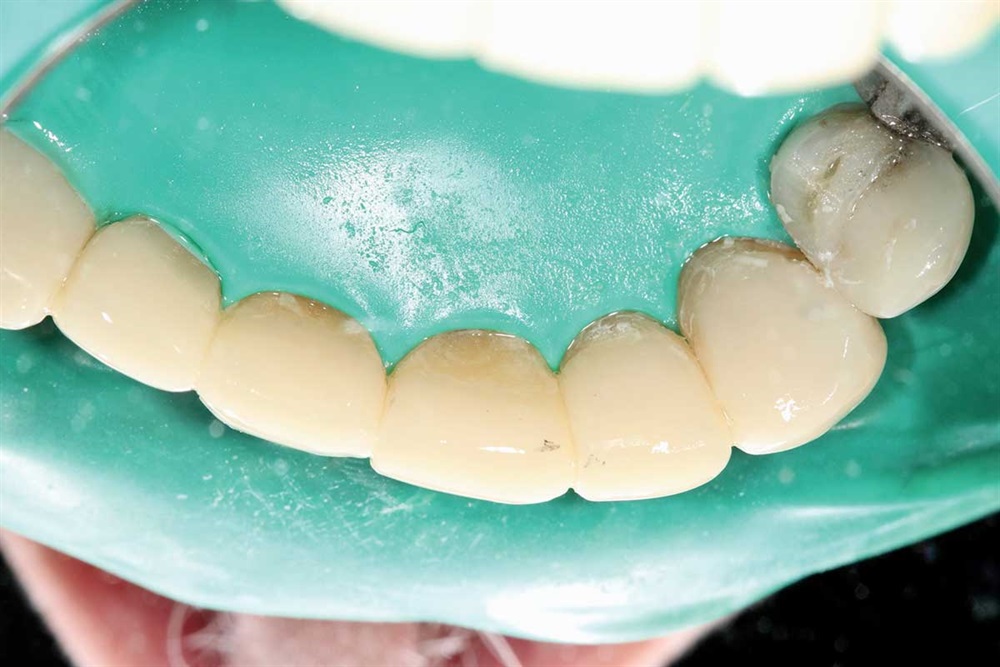

Fig. 36: All done adding my pound of composite.

Fig. 37: For the upper first bicuspids, I added to the buccal cusp and made them longer and more prominent for aesthetics using only Z250 A2.

Fig. 38: Right side and polished with 3M’s Sof-Lex Superfine disk.

Fig. 39: Left side, the same polish.